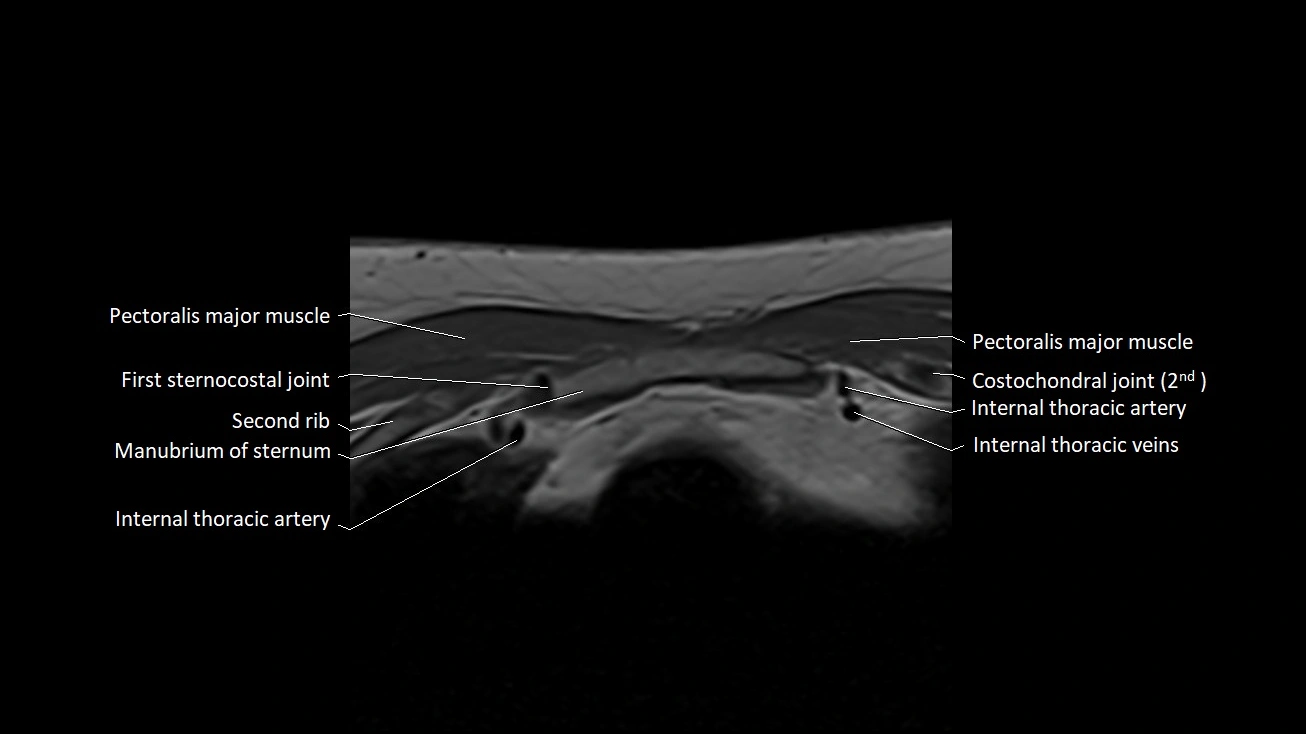

MRI images

image